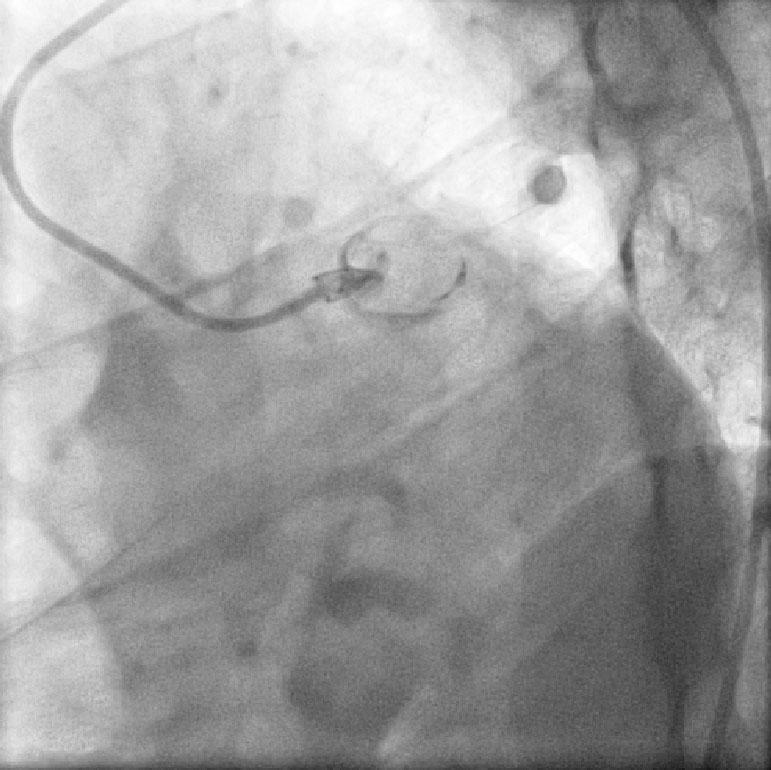

CABG in Kawasakis with Coronary Aneurysms

Angiogram prior to Primary PTCA